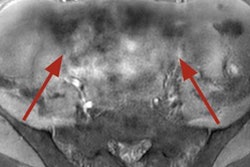

The investigators analyzed a teleradiology platform used across the U.S. that allows radiologists working from home to log in, view x-ray, CT, or MRI exams that need interpretation. Radiologists can then choose which of these exams to read and report on.

The research included more than 2.1 million imaging exams across 251 procedures conducted in 62 hospitals. Approximately 115 radiologists read the exams, which were categorized as "routine," "stat," "expedited," and "hyperacute." Most studies were classified as "stat" (that is, acute but not life-threatening).